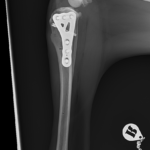

大型犬の前十字靭帯疾患(慢性経過)に対するCBLO #254 大型犬のCrCLDの患者さんに3.5 Rita Locking CBLOで対応しました。今後はリハビリテーションが非常に重要になります。生涯にわたって膝関節のケアを行なっていく必要があります。 症例カテゴリー 放射線治療整形外科軟部組織外科脳神経外科内科腫瘍外科救急・集中治療リハビリテーション科腫瘍内科内視鏡科脳神経科呼吸器外科中医・漢方猫の腎移植循環器科